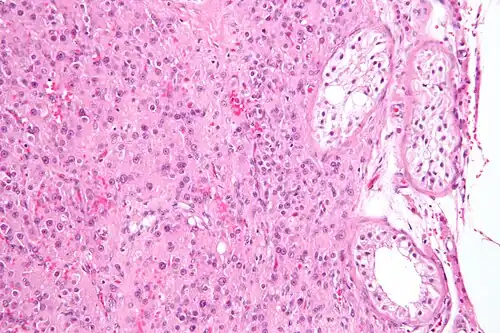

| Histopathology of a Leydig cell tumor, high magnification, H&E stain, showing typical features.[1] | |

High magnification micrograph of a Leydig cell tumour. H&E stain.

High magnification micrograph of a Leydig cell tumour. H&E stain. -